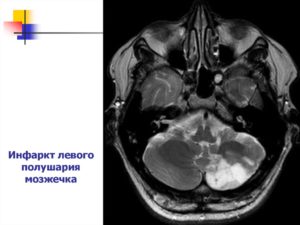

Изолированный инсульт мозжечка

Изолированный инсульт участка гемисферы мозжечка, когда затронуто кровоснабжение из задней нижней мозжечковой артерии, проявляется комплексом вестибулярных расстройств, самым частым их которых является головокружение. Кроме того, больные испытывают боли в затылочной области, жалуются на тошноту и нарушение походки, страдает речь.

Диагностика мозжечкового поражения

Составить полную клиническую картину заболевания можно только в стационаре. Доктор собирает анамнез, назначает МРТ или КТ головного мозга для выявления очагов поражения. Пациент сдает анализы и проходит ЭКГ. Диагностика позволяет установить тип инсульта и подобрать оптимальные методы лечения.